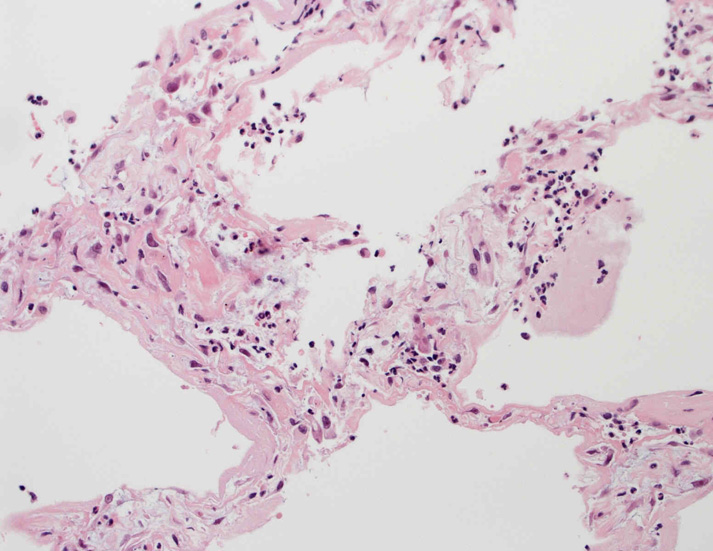

肺毛細血管炎 capillaritis

肺胞壁に多数の好中球浸潤。肺胞腔内に出血。 capillaritisが起こるWegener' granulomatosis劇症型には, なかなか肉芽腫性病変を見つけることは難しい

capillaritisの組織所見*17

Fig.01 capillaritisと肺胞出血Fig.02 Fig.01拡大像